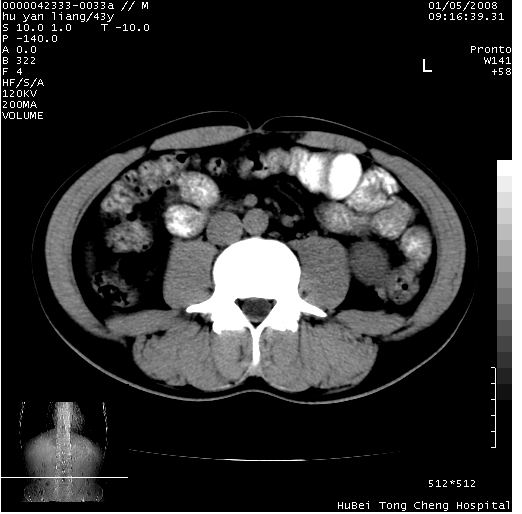

患者 男,43岁。右上腹不适1年余。既往有“肝右叶肝脓肿”病史,经保守治疗后痊愈。

b超提示:1)肝右叶肝内胆管结石。2)肝右叶占位性病变待排。

上中腹部ct轴位平扫+增强扫描(层厚10mm,螺距1.0,重建间隔10mm),图像如下:

肝右上叶偏后方较大团片状钙化灶,支持:肝脓肿后遗改变!